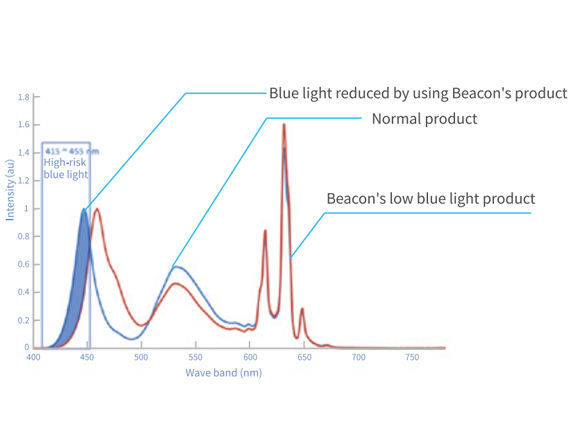

La luz azul pertenece a la luz de onda corta en el espectro, que puede generar mucha energía y existe en gran cantidad en la pantalla. La exposición prolongada a la luz azul es la principal causa de degeneración macular. La pantalla de diagnóstico Jufeng low Blue light puede reducir la luz azul dañina en más de un 50%, y conducirá significativamente al riesgo de muerte y degeneración macular.

Tecnología de baja luz azul

La luz azul es una parte de la luz de onda corta en el espectro, que es abundante en la pantalla normal. La exposición prolongada a la luz azul es la principal causa de la maculopatía. Los principales síntomas de la maculopatía son el deterioro visual central y la deforvisual. Más del 50% de la luz azul se puede reducir por la tecnología de luz azul baja, el riesgo de degeneración macular se puede reducir significativamente.